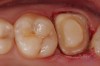

A Class IN maxillary bicuspid was previously restored with a fiber post and an all-porcelain crown (Figure 1). The forces of the oral environment resulted in fracture of the fiber post and crown failure. The remaining fiber post in the root was removed, and anti-rotational areas were prepared for a cast post (Figure 2). A gold cast post was constructed at a dental laboratory, using an indirect technique (Figure 3). A porcelain-fused-to-metal (PFM) crown was constructed with a bevel finish to provide a ferrule and reduce forces on the post (Figure 4 and Figure 5).

Figure 5  The final crown.

Figure 5